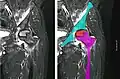

Cabeza de fémur, abajo del corte de cartílago en la parte superior, se puede ver la osteonecrosis

La mayoría de las veces los doctores ortopédicos diagnostican la enfermedad excepto en la mandíbula, donde normalmente es diagnosticado y tratado por cirujanos dentales y maxilofaciales. El examen de elección es la resonancia magnética, capaz de detectar osteonecrosis antes de que haya daño significativo en el hueso.